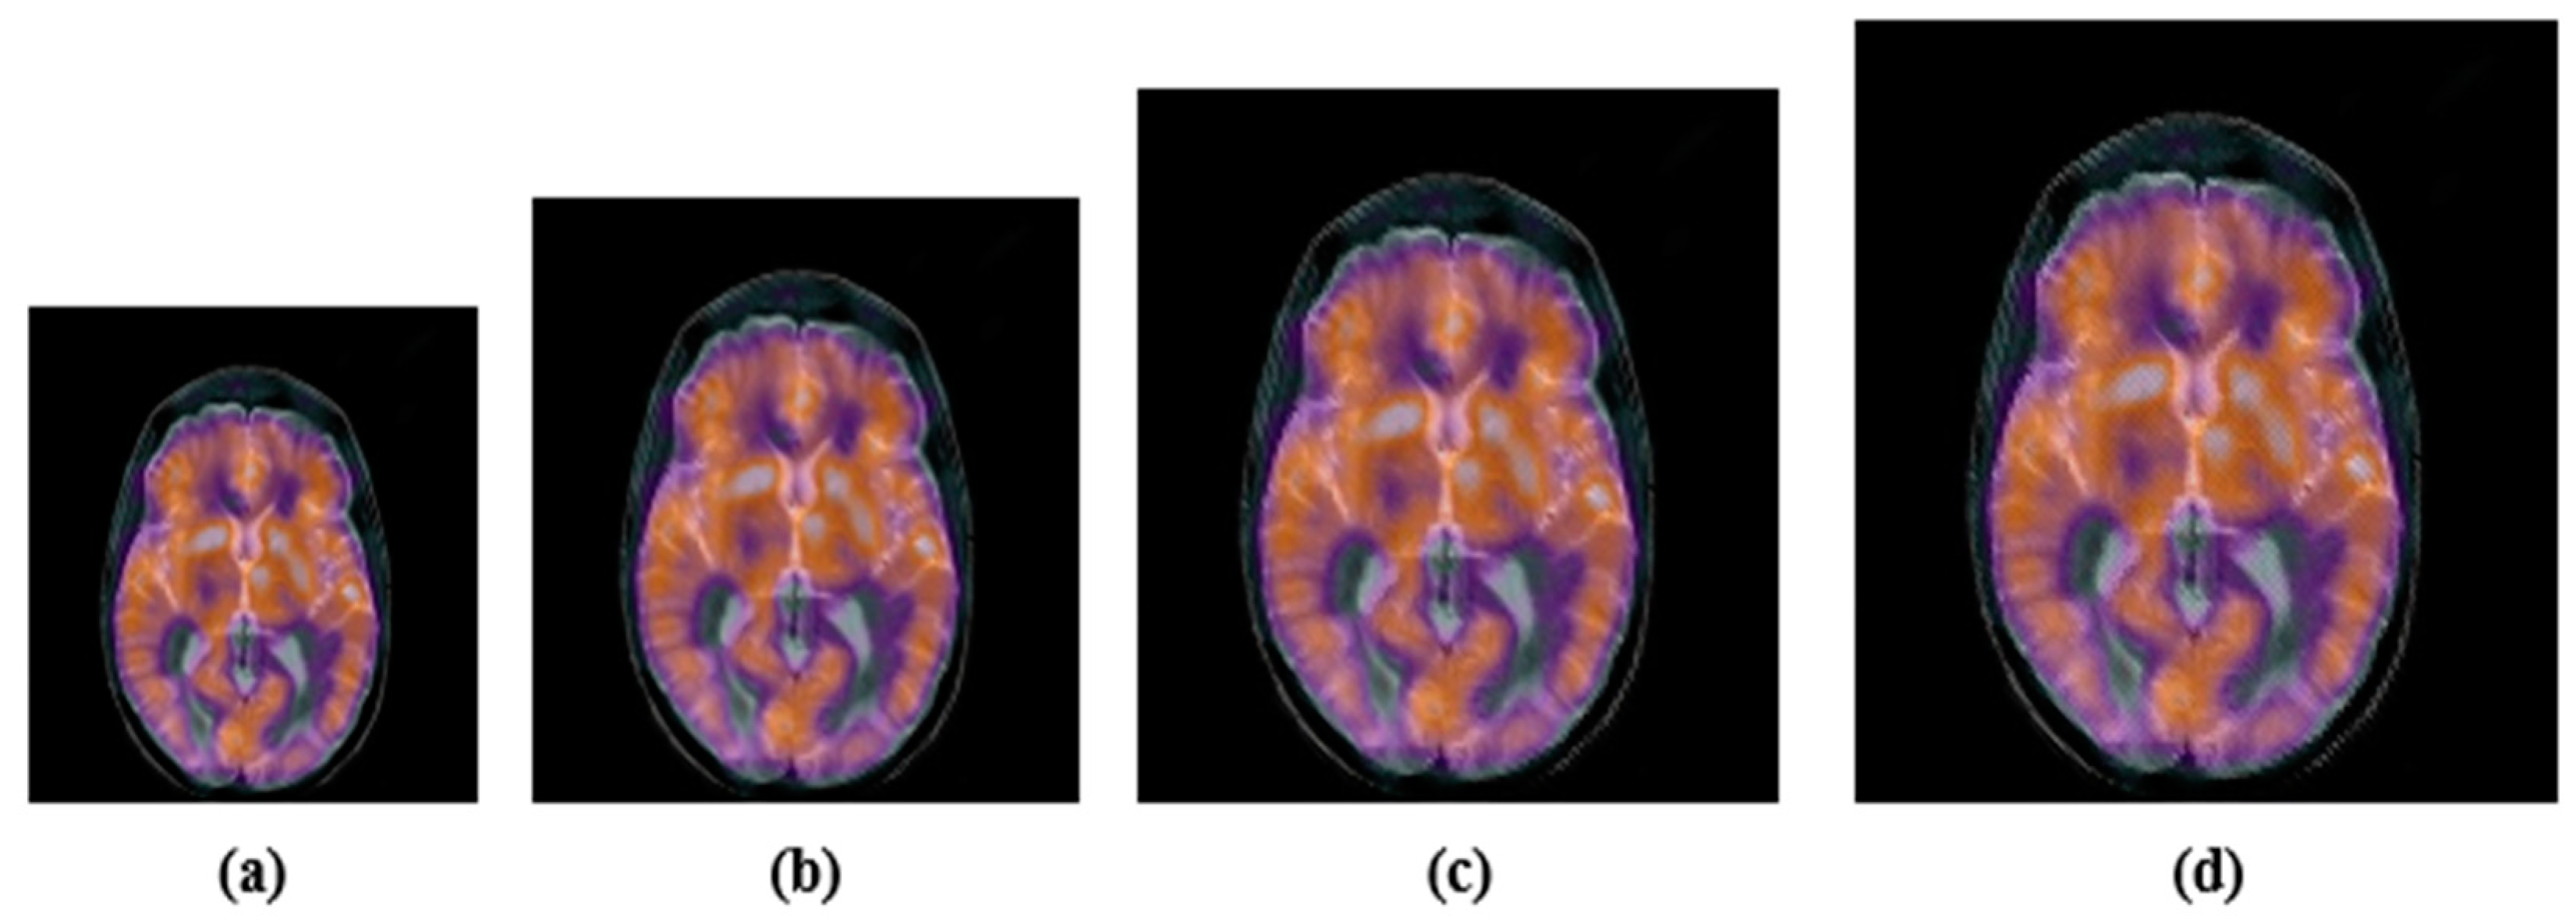

4.2.2. Geometric Attacks

| Image rotation | Rotation angles: 50, 150, 250, 450 |

| Image scaling | Scaling factors: 0.5, 0.75, 1.25, 1.5 |

| Length–width ratio changing | Factor (1.0, 0.75) and (0.5, 1.0). Note: The parameters refer to vertically and horizontally scaling. |